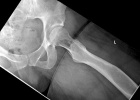

25 year old female c/o 4 month history of L hip and thigh pain, sharp and throbbing in nature. No h/o trauma. Hip injection did not result in any pain relief. Uses crutches for ambulation and Lortab for pain relief. Does not have any fever or chills.